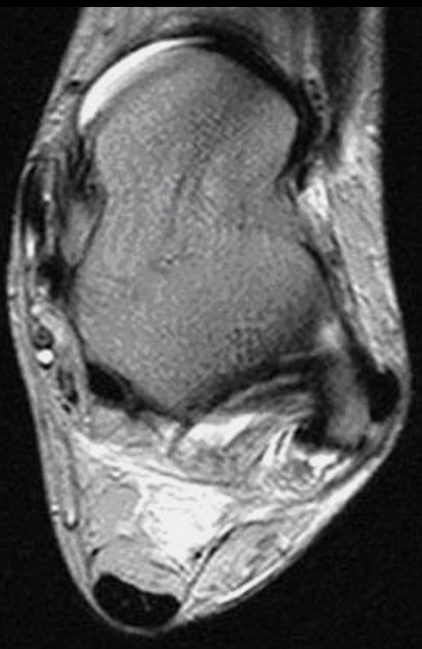

✨Up Next in our Member Spotlight Series - featuring Dr. Rocky Saenz! His passion for education has inspired numerous medical students and radiology residents. Dr. Saenz has made significant strides for DOs and radiologists, enhancing their recognition in the medical field.